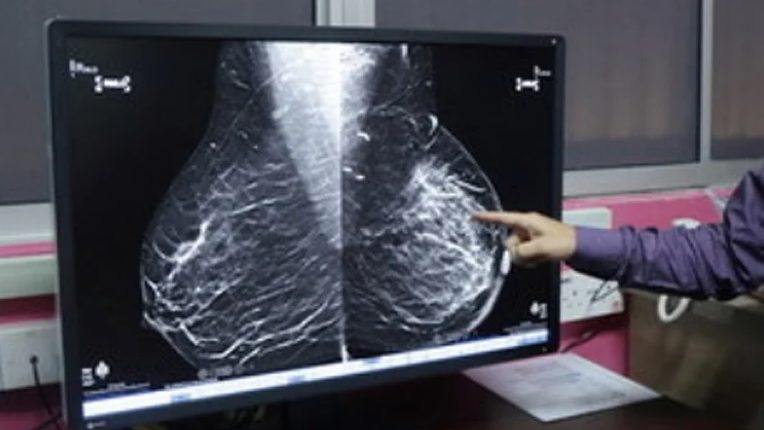

冠病影响癌症早期筛查 NCSM:乳腺结肠癌最多

冠病大流行导致许多癌症患者,尤其是乳腺癌和结肠癌患者难以接受早期筛查,从而无法更早地发现疾病。